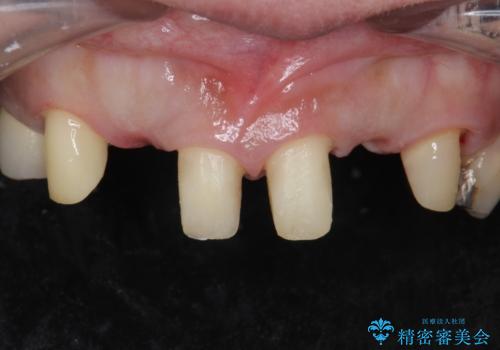

②の方を選択されましたので被せ物治療を行いました。

また、左上の犬歯の根の再治療も行いました。

最終的な被せ物は抜歯を行なってから半年経ってから形を整えて型取りを行います。